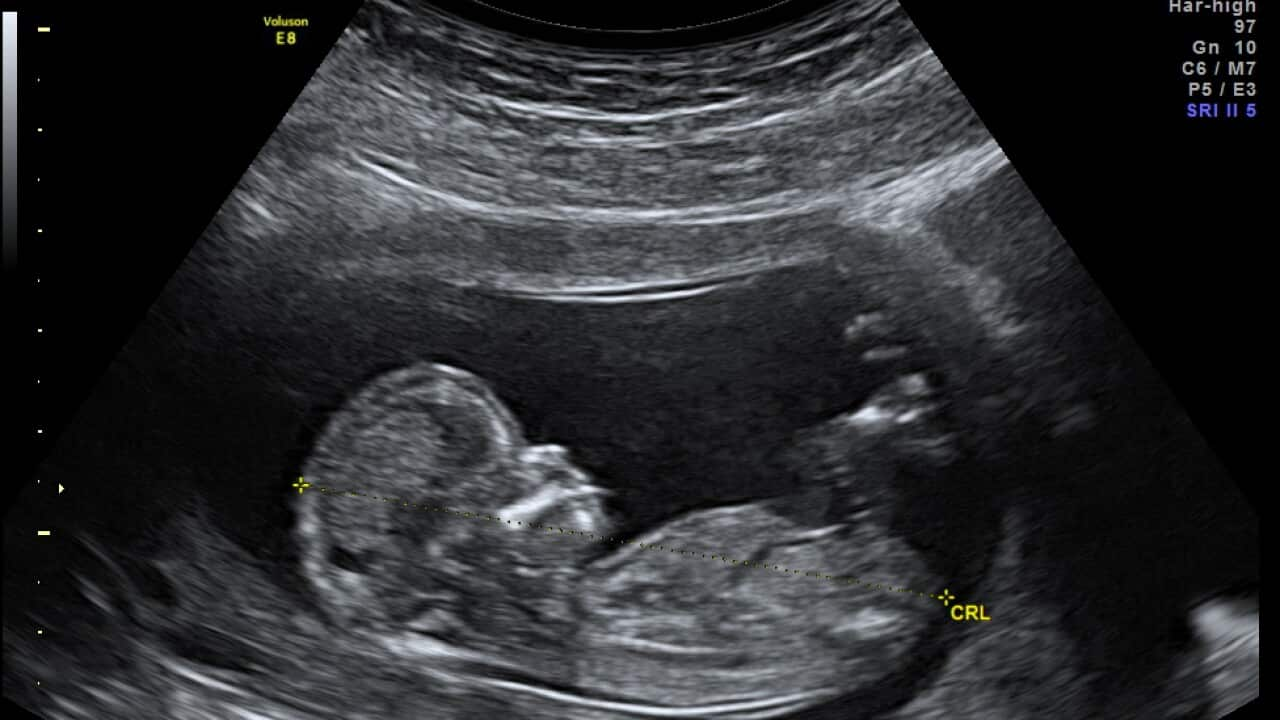

أشارت دراسة جديدة أن بإمكان السيدات الحوامل وبنسب كبيرة الحؤول دون وفاة الجنين في رحمهن اذا ما اتبعن بعض الخطوات.

عن ولادة جنين ميت والخطوات لتفادي حدوث ذلك، التقت سناء وهيب اخصائية التوليد والعقم الدكتورة وفاء سامن وسألتها أولا عن العوامل المؤدية الى وفاة الجنين داخل الرحم في الشهور الأخيرة من الحمل.

أشارت الدكتورة أن بإمكان الأم مراقبة حركة الجنين ودعت السيدة الحامل الى استشارة الطبيب في حالة غياب حركته.